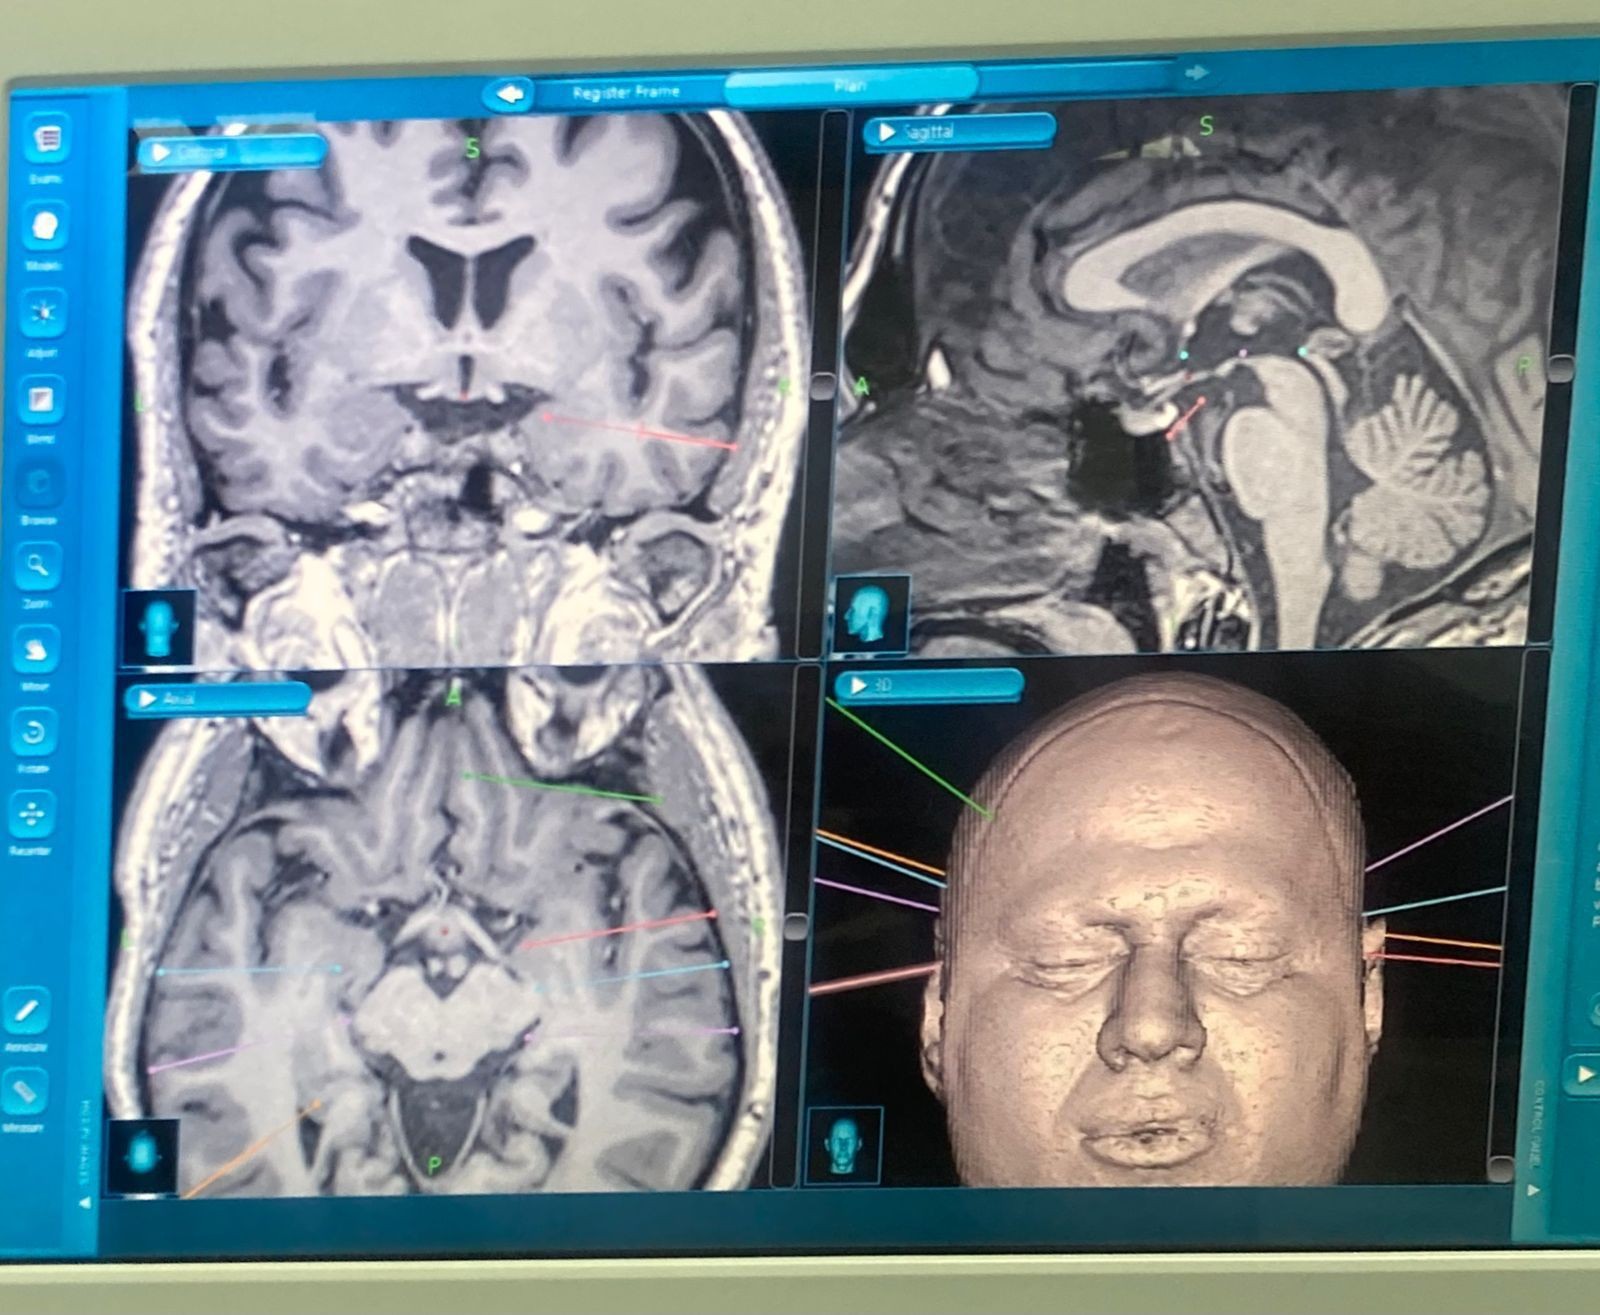

نجح فريق طبي من مركز العلوم العصبية في مستشفى الملك فهد التخصصي بالدمام بإجراء عملية صرع نوعية لمواطن في العقد الخامس من العمر في عملية جديده تمت من خلال التدخل الجراحي المحدود باستخدام .StereotacticEEG وتعد الأولى من نوعها في المنطقة الشرقية .

وأوضح رئيس تشغيل مستشفى الملك فهد التخصصي بالدمام الأستاذ شريف عدنان عمر أن العملية تمثلت في زراعة حساسات رفيعة وعميقه داخل الدماغ وذلك بادخالها عن طريق فتحات في الرأس لا يتجاوز قطرها 3 مليمتر . وتعد أحدث وسائل التشخيص لحالات الصرع المستعصية ، حيث تم أخذ المريض بعد  وضع الحساسات في أماكنها الصحيحة داخل الدماغ  لوحدة مراقبة الصرع  لتبدأ عملية التخطيط الكهربائي  لتحديد مكان البؤرة الصرعية المسببة للتشنجات .

وبين الدكتور زياد الثاني أن هذا الأسلوب الجراحي SEEG يتطلب بعض الترتیبات المسبقه من خلال  تحديد أماكن زراعة الحساسات عن طريق التخطيط الكهربي للدماغ وأشعة الرنين المغناطيسي، وتحديد مسارات زراعة الحساسات بدقه في الدماغ باستخدام الجهاز الملاحي ، وأشارات الدكتوره رائده البرادعي إلى أن تخصصي الدمام يمتلك الكفاءات المميزة والتجهيزات الطبية التي تمكنه من تحقيق الإنجازات على مستوى المملكة والشرق الأوسط من خلال الدعم الامحدود من الدوله للقطاع الصحي